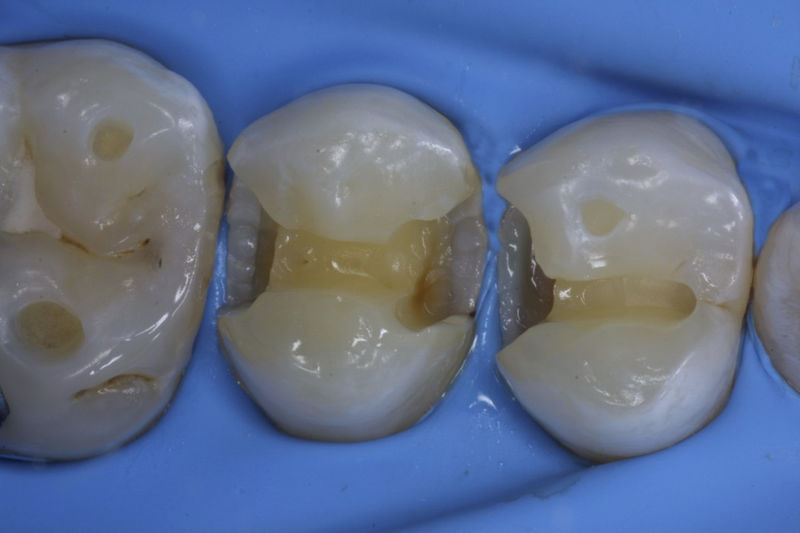

Restauraciones fabricadas en el laboratorio con materiales estéticos, los cuales cubren de manera parcial dientes posteriores. Se utilizan primariamente para restaurar dientes con caries, fracturas y/o defectos amplios. Para poder enviar el caso al laboratorio se toman impresiones utilizando materiales de impresión o técnicas modernas digitales.